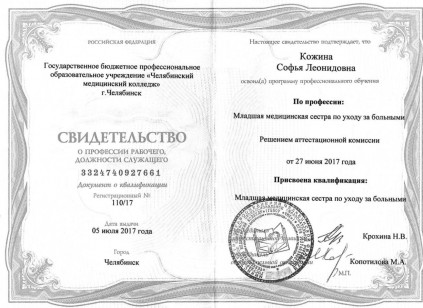

Сертификаты